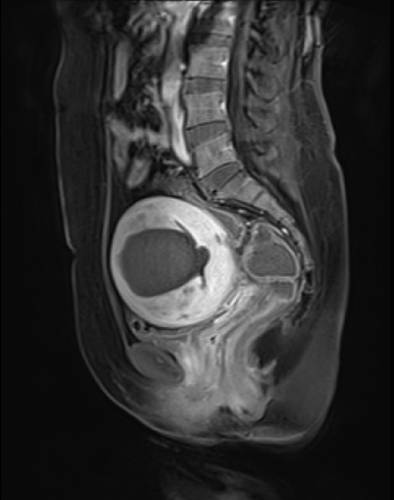

- ▲ 하이푸시술로 치료를 받은 자궁선근증 환자의 자궁 MRI 촬영 모습ⓒ강남베드로병원

두 질환 모두 초음파로 진단하는데 자궁선근증의 경우 자궁이 비대칭적으로 켜져 있지만 자궁근종과 같이 뚜렷한 혹은 보이지 않는다. 초음파로 정확히 병변이 보이지 않거나 확인이 어려운 경우에는 MRI를 통해 정밀한 진단이 가능하다.